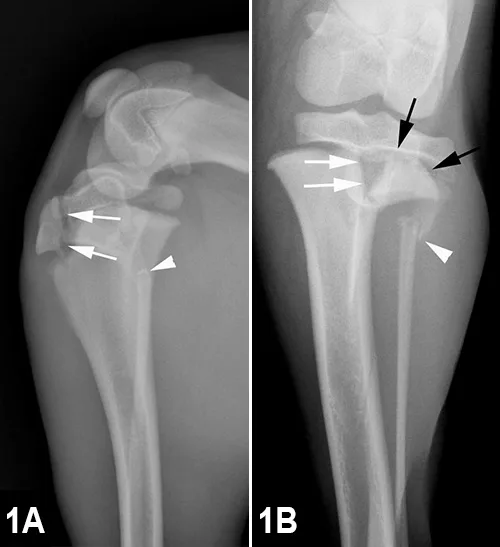

Radiographs: Lateral (Figure 1A) and cranio–caudal (Figure 1B) views of the right stifle

Radiographic Findings: There is a vertical fracture of the right proximal tibial metaphysis (white arrows); the remaining metaphysis is displaced medial to the epiphyseal portion of the tibia, indicating a physeal fracture (black arrows). The epiphysis is spared, and no joint effusion is detected. A fracture of the proximal fibula and medial displacement are also observed (white arrowhead).

Diagnosis: Thie tibial fracture is classified as a Salter–Harris type II fracture, the most common fracture type involving the physis. Physeal fractures must be identified, as angular limb deformities and joint incongruities can result from premature closure of a physis, particularly when involving the radius or ulna.